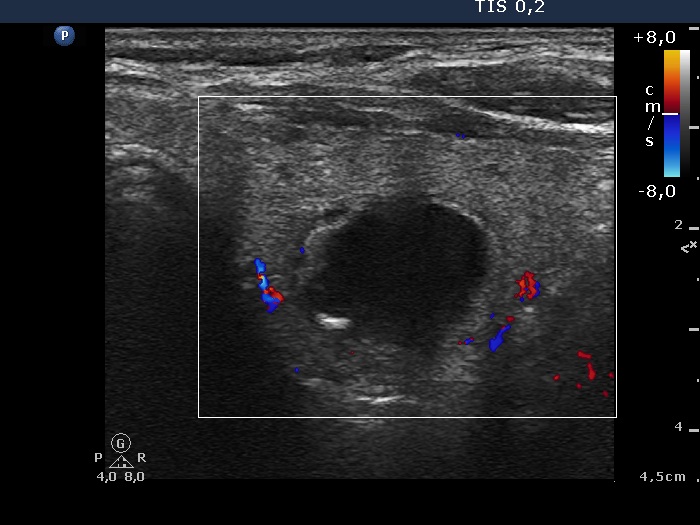

The composition of the nodule - case 1792 (ultrasonographic picture 11)

Right lobe, longitudinal scan